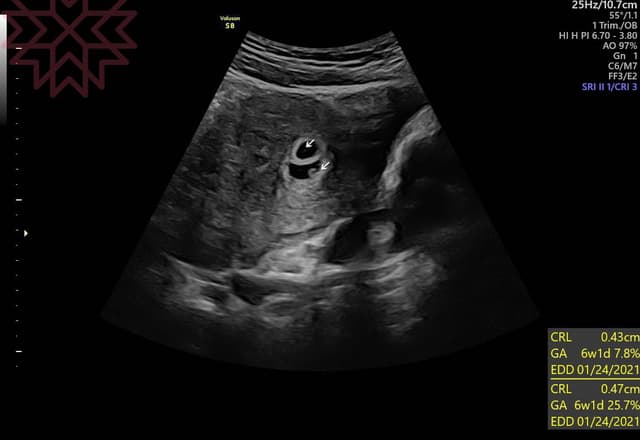

About Press Copyright Contact us Creators Advertise Developers Terms Privacy Policy & Safety How works Test new features Press Copyright Contact us Creators6w1d 心拍確認できず 診察してきました~ ※エコー画像あり いやな方はスルーしてください。 胎のうは大きくなっていて、血液検査の結果もまずまず順調だったけど 胎芽&心拍が確認できませんでした。 。 。 今日の先生から 「来週の診察で心拍が (参考)1日前のの6w1dでの心拍確認済みの割合は、75%でした。 6w1d心拍確認できない割合、胎嚢・胎芽の平均的な大きさを調査 今回調査した50名の妊婦の内訳は、出産が44名、流産が6名でした。 出産できた44名のうち、6w2dで心拍確認できたのは28名です。

妊娠6w1dで病院に行ったところ胎嚢が小さいと言われ、まだ心拍の確認が出来ないと言われてしまいました。 5w1dで胎嚢の大きさは58mm 今回は6w1dで103mm で胎芽も見えませんでした。 流産の可能性はありますか?? (30代/女性) 6w1d 胎芽、心拍確認できませんでした person 30代/女性 lock 有料会員限定 前回5w1dで胎嚢6mmで小さめだったのですが、hcgが3000越えていたので喜んだのもつかの間。 今回6w1dで胎嚢16mmで大きくなっていたのに空っぽでした。 卵黄嚢も胎芽すらも見え 心拍は何週目に確認できましたか? 妊娠初期の妊娠の大まかな目安は8週までに胎児心拍が認められることです。 そのため、 妊娠検薬で早めに妊娠がわかったとしても、 その後心拍確認まで何度も病院に足を運ぶことになります。 およそ1週間ごとに診察

心拍確認 6w1d 今日(6w1d)は前回の(5w2d)の胎嚢確認から6日ぶりにklcに行きました。前回はhcgが843と伸びてはいたものの、まだ低い状態でした。今日はhcgはいくつになっているんだろう?と心配していましたが、診察前の採血はなし? でした。妊娠6w1d おなまえ あい ねんれい 32 妊娠週 6w1d 先生には6週6日くらいの大きさですね、と言われました。 25ミリです。 次回2週間後に行って心拍確認出来たら、母子手帳貰ってきます。 スクスク育ってくれますように おなまえ ゆき心拍確認ができる週数の目安はおおむね 6w~7w といわれています。 一般的に6wで確認できなくても問題にはならず、7w台で確認できないと心配なようです。 私の場合、5w1dで無事胎嚢は確認できたものの、着床が遅れたのが原因で週数にしては小さめの結果でした。

妊娠週 6w1d 6wに入ってすぐ、つわりが出始めました。 卵黄嚢と胎芽がみえ、拡大してもらうと心拍も確認できました。 次回は二週間後、成長が楽しみです。 里帰り出産のため、里帰り先の産婦人科に電話しました。 人気のある病院はすぐに埋まって 初めての顕微授精で人生初の陽性判定をいただきました。 5W3Dで胎のう確認できたのですが、6W1Dで心拍確認できませんでした。 不妊治療クリニックの先生は「6週で見えないのは厳しい、来週になっても見えなかったら残念ですが・・・」と言われてしまいました。 体外(顕微)の場合は、周期が確定しているため、やはり6Wで心拍確認できないと残念な結果になる6w1d胎芽・心拍確認 不妊治療 妊娠のかくかくしかじか。

6w2d心拍確認 こんにちは この日は、不妊治療クリニックで心拍確認の日。 前回妊娠したときの子は、この日は確認ができず、1週間後に確認ができました。 なのでこの日も、もし確認できなくても焦らないように、と自分に言い聞かせて臨みました そして内診の結果・・・ 無事に心拍確認できました 嬉しいというより、安堵です CRLは35ミリでした!妊娠週 6w1d 排卵日が特定できているので、確実に6w1dのエコーです (^^)元気な心拍と2mmの赤ちゃんが確認できました! 2人目の妊娠なので、まだ1歳10ヶ月の長男を抱っこしたり追いかけ回したりでゆっくりできないので、赤ちゃんが心配ですが生命力を信じてマタニティライフを楽しめたらと思います! 先生にも、着床の位置も大きさもいいし、胎嚢の形も卵黄嚢も6w1d 22日、判定日から2回目6w1dでの診察でした。 先週先生に6wで心拍見えると思いますのでと言われていたので、それからと言うもの日々心拍について調べてしまう私 (>_

6w1dは心拍確認できましたか?☺️7wで行くか迷います🤔🤔 6w1dは心拍確認できましたか? ☺️ 7wで行くか迷います🤔🤔 2月8日 お気に入り 妊娠6週目 妊娠7週目 6w1d 心拍確認済みの方には胎芽のサイズだけ報告している人も多いので、実際はもっといるかもしれません。 胎芽については、個人差が激しいものの概ね32mm前後に分布している印象です。 もちろん、胎芽が見えなかった方もたくさんいます。 体外受精の場合 胎嚢:最小119mm 最大193mm 胎芽:最小14mm 最大43mm 体外受精の方々は、全員6w0d時点で胎芽が確認できてい